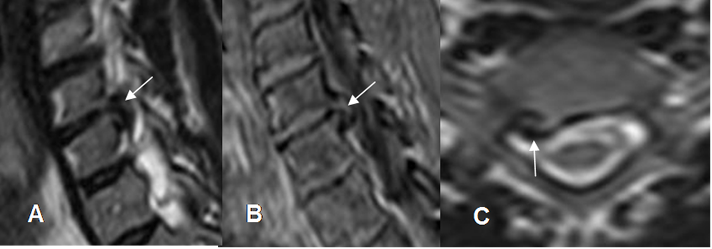

Fig 48. Osteofitos.

A: RM sagital en T2. Area hipointensa que ocupa la región paramediana, a diferenciar entre hernia u osteofitos.

B: RM sagital en gradiente eco y C: RM axial en T2. Lesión con borde hipointenso a nivel paramediano derecho, que corresponde a la cortical de un osteofito.